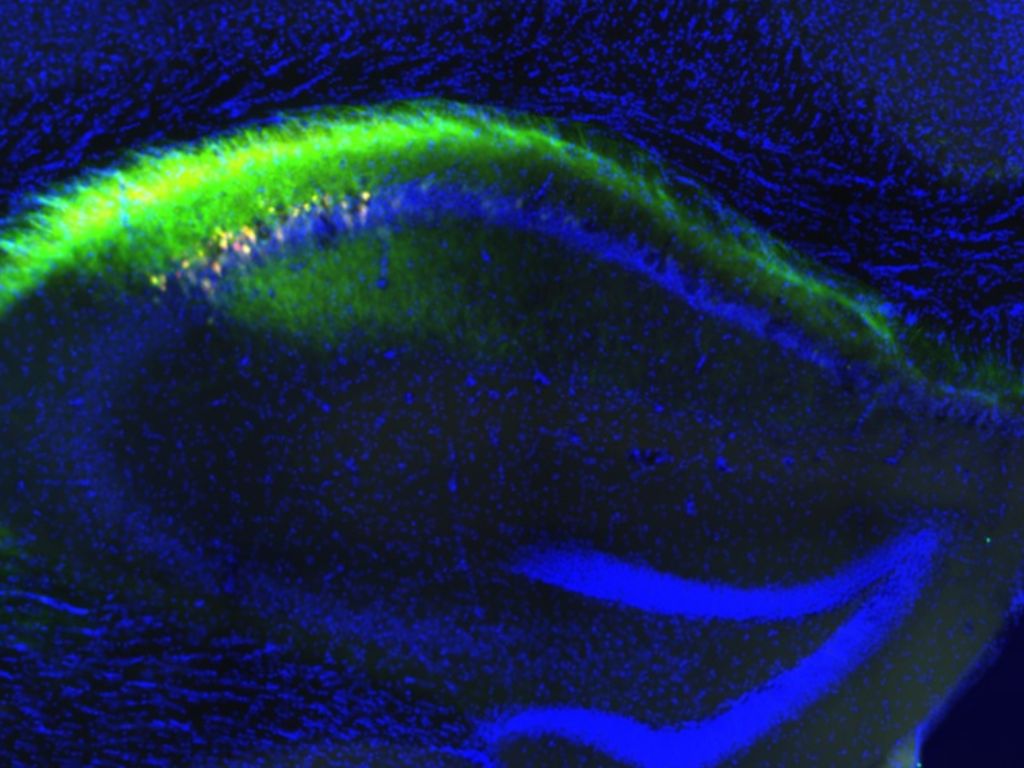

Un estudio liderado por el Instituto de Neurociencias (IN), centro mixto del CSIC y la Universidad Miguel Hernández, ha descrito por primera vez una vía neuronal específica fundamental para la memoria espacial. El trabajo, publicado en la revista Cell Reports, identifica una proyección que conecta la región CA1 del hemisferio derecho con el subículo del hemisferio izquierdo en el hipocampo. Esta investigación demuestra que la comunicación entre ambos hemisferios es una condición mecánica necesaria para que el cerebro pueda integrar la información sobre la ubicación de objetos y la orientación en el espacio.

Para validar la función de este circuito, el equipo dirigido por el Dr. Félix Leroy empleó técnicas de optogenética, permitiendo el bloqueo selectivo de esta conexión en modelos animales. Los resultados revelaron que, al interrumpir este "puente" neuronal, los sujetos presentaban dificultades severas en tareas de memoria espacial y toma de decisiones, mientras que otras funciones como el reconocimiento de objetos o los niveles de ansiedad permanecían intactas. Este hallazgo confirma que la conexión posee una especialización funcional concreta dentro de los procesos cognitivos.